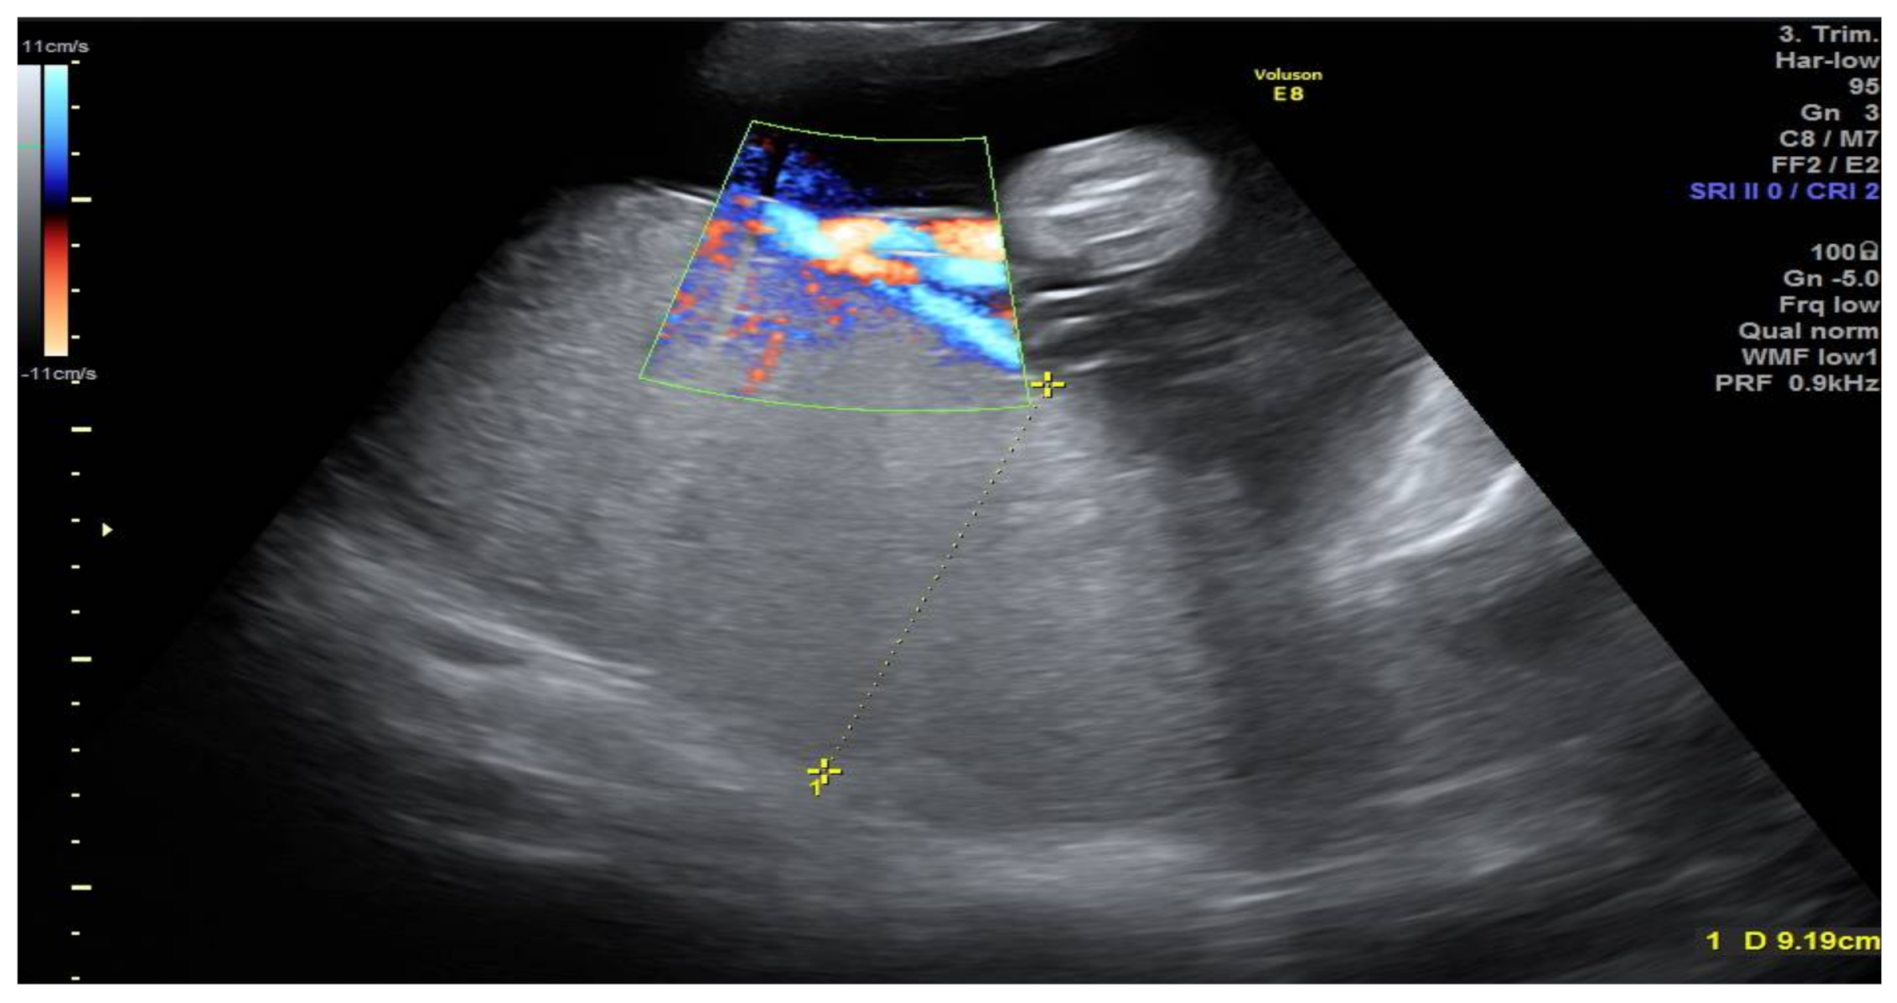

2. Case Presentation